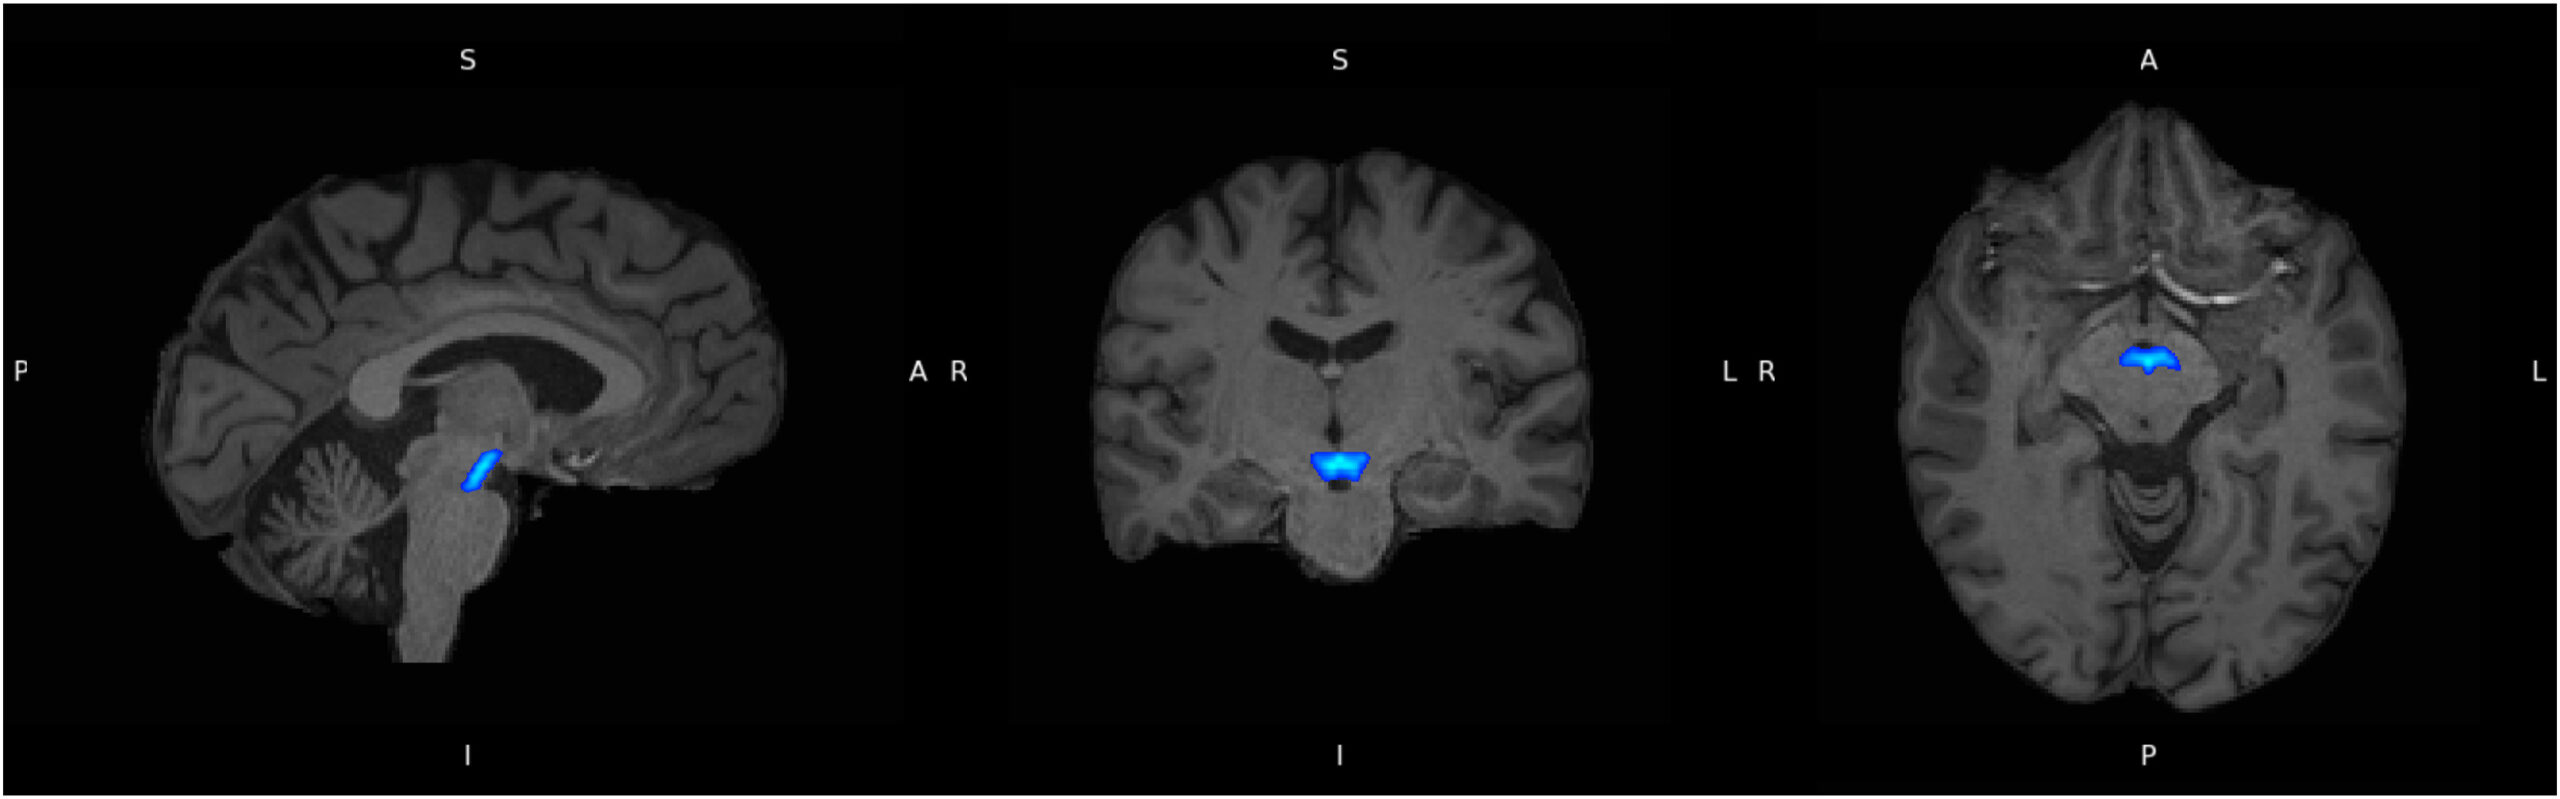

In a large scale imaging study using data from the UK Biobank, researchers identified distinct magnetic resonance imaging markers in the ventral tegmental area, a dopamine rich brain region involved in motivation and reward processing, that were associated both with a history of major depressive disorder and with current symptom severity.

The ventral tegmental area sits at the centre of this network, regulating motivation, pleasure and mood through dopaminergic signalling. Despite its importance, the region has been difficult to study in detail because of its small size and complex anatomy.

In this study, researchers used advanced magnetic resonance imaging techniques to examine whether imaging derived markers sensitive to neuroinflammation and microstructure in the ventral tegmental area were associated with depression diagnosis and symptom severity.

MRI metrics extracted from the ventral tegmental area included free water and isotropic volume fraction, which are sensitive to extracellular processes such as inflammation, as well as intracellular volume fraction and orientation dispersion index, which reflect microstructural properties. Magnetic susceptibility was also measured as an indirect marker of iron accumulation associated with chronic inflammation.

Ventral tegmental area (in blue), delineated using the Levinson-Bari Limbic Brainstem Atlas, displayed on coregistered participant T1 images. A, anterior; I, inferior; L, left; P, posterior; R, right; S, superior.